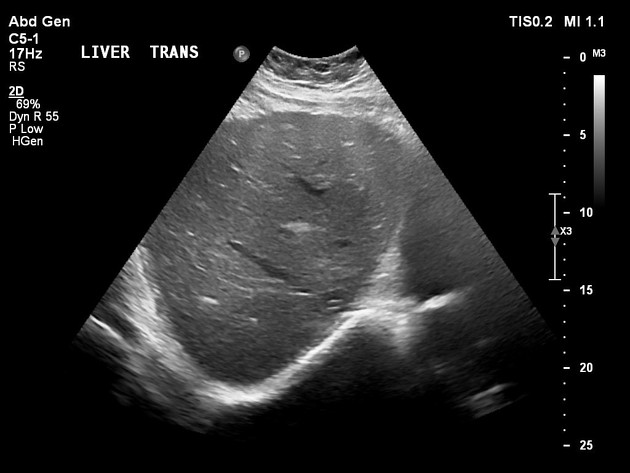

Abcess